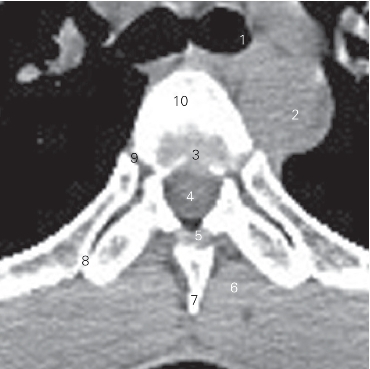

图2-1 经第6胸椎椎体的横断层CT图像(软组织窗)

1 左主支气管 left principal bronchus 2 胸主动脉 thoracic aorta

3 第6胸椎间盘 6th thoracic intervertebral disc

4 胸髓 thoracicc cord 5 黄韧带 ligamentum flavum

6 竖脊肌 erector spinae 7 棘突 spinous process

8 肋横突关节 costotransverse joints 9 肋头关节 joint of costal head

10 第6胸椎椎体 6th thoracic vertebral body